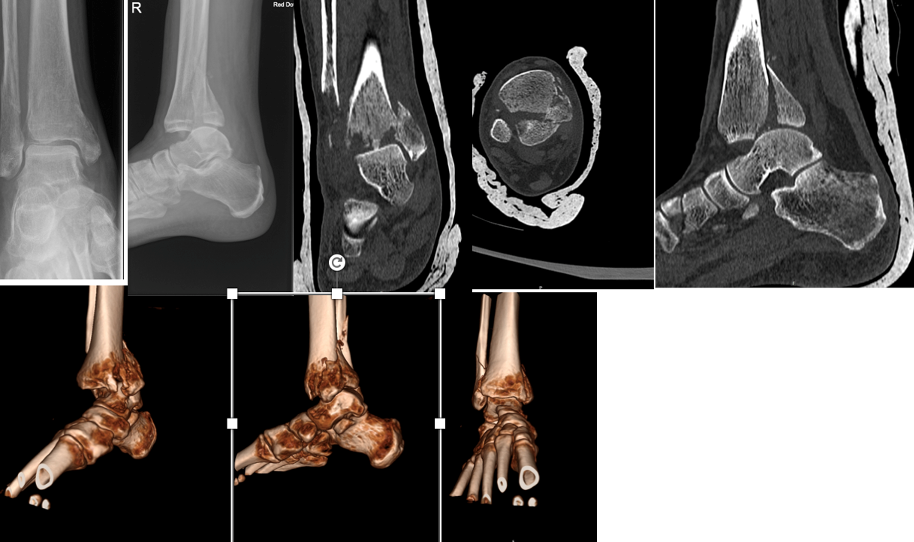

Management of bimalleolar fracture is quite standard however when it comes to trimalleolar fracture, management of posterior malleolar fragment has notable variability in surgeon’s practice. Access to the advance imaging helps better understanding of fracture’s configuration and planning (Fig1). Different approaches and techniques have been described to address these fractures. In this Study we looked at these fractures treated with fragment specific fixation and reported functional and radiological outcome.

Fig 1 Radiographs and CT scan demonstrating different patterns of trimalleolar fractures.

All patients presented to our department with trimalleolar ankle fractures from October 2021-March 2023 were included in the study. We excluded the patients from study who were under 18 years of age, does not require posterior malleolus fixation or need fixation method other than plate osteosynthesis. On presentation trimalleolar fractures were identified on Anterior-posterior and lateral radiographs. Patient presented with subluxation or dislocation of ankle needing manipulation were treated by the on-call team Post reduction Splinting (Back slab) was applied and radiographs were obtained to assess the reduction. Subsequently computed tomography (CT) was acquired with coronal, sagittal, axial planes, and 3D reconstruction. The fracture fragments were evaluated using Mason & Molloy classification14 and divided into subtypes 1, 2a, 2b and 3 fractures (Fig 2). Definitive fixation was delayed until the soft tissue settles. If concern with soft tissue and unstable fracture not able to maintain the position in back slab, temporary external fixation was applied until soft tissue settles. Osteosynthesis using fragment specific implant (VolitionTM) and relevant surgical approach was performed. Post operatively these patients were followed in outpatient department at 2, 6,12,26 weeks. They were clinically assessed for any pain, stiffness, infection, nerve damage, CRPS metalwork irritation or failure, and clinical union Functional assessment was carried out using The Manchester-Oxford Foot Questionnaire (MOXFQ) and Foot and ankle disability index (FADI). Anterior -posterior, lateral and mortise radiographs were taken to assess the fixation, adequacy of reduction and radiological union.